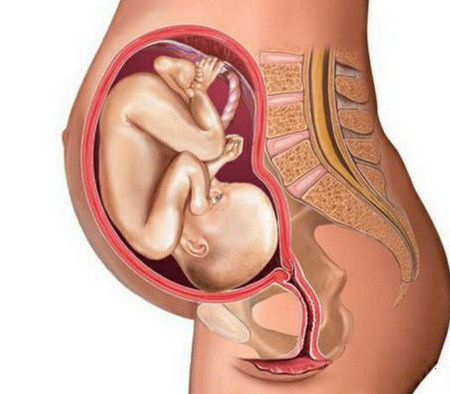

胎儿头部大小、体位

产道的条件合适了,也不一定能够顺产,胎儿的大小体位也是影响是否能够顺产的关键条件。如果宝宝的体重超过4公斤的话就会比较容易造成难产,有可能采取剖腹产,另外宝宝的胎位不正也会在一定程度上影响到顺产,宝宝的头部发育过大的话,就会造成入盆困难,也不容易顺产。